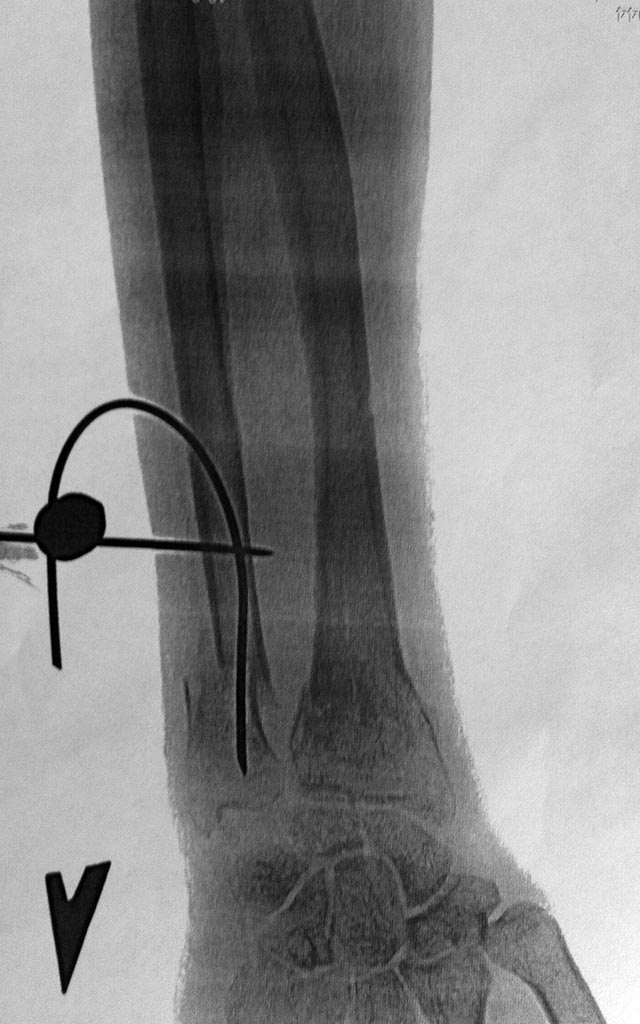

И боковая проекция

Кликните для загрузки файла image.jpg

1477KB (1512718 bytes)

Через 8 недель, после удаления конструкции

1184KB (1213360 bytes)

- сравнивать правильнее было бы не просто в гипсе, а с фиксацией спицами и в гипсе; репозиции отломков локтевой нет; сращения к 8 неделе нет - мозоль снимке в прямой проекции еле видна.

Но, что касаемо репозиции, нельзя сказать что ее вообще нет. Сохранение смещения на ширину кортикала я считаю допустимым. Длинна сохранена, никаких курваций нет. Внешне, так вообще никаких деформаций. А рентгенологическая картина всегда отстает. На таких сроках, при таком переломе вряд ли Вы "потеряете" линию перелома. Обратите внимание, что и на лучевой кости линия внутрисуставного перелома видна отчетливо.

1502KB (1538499 bytes)